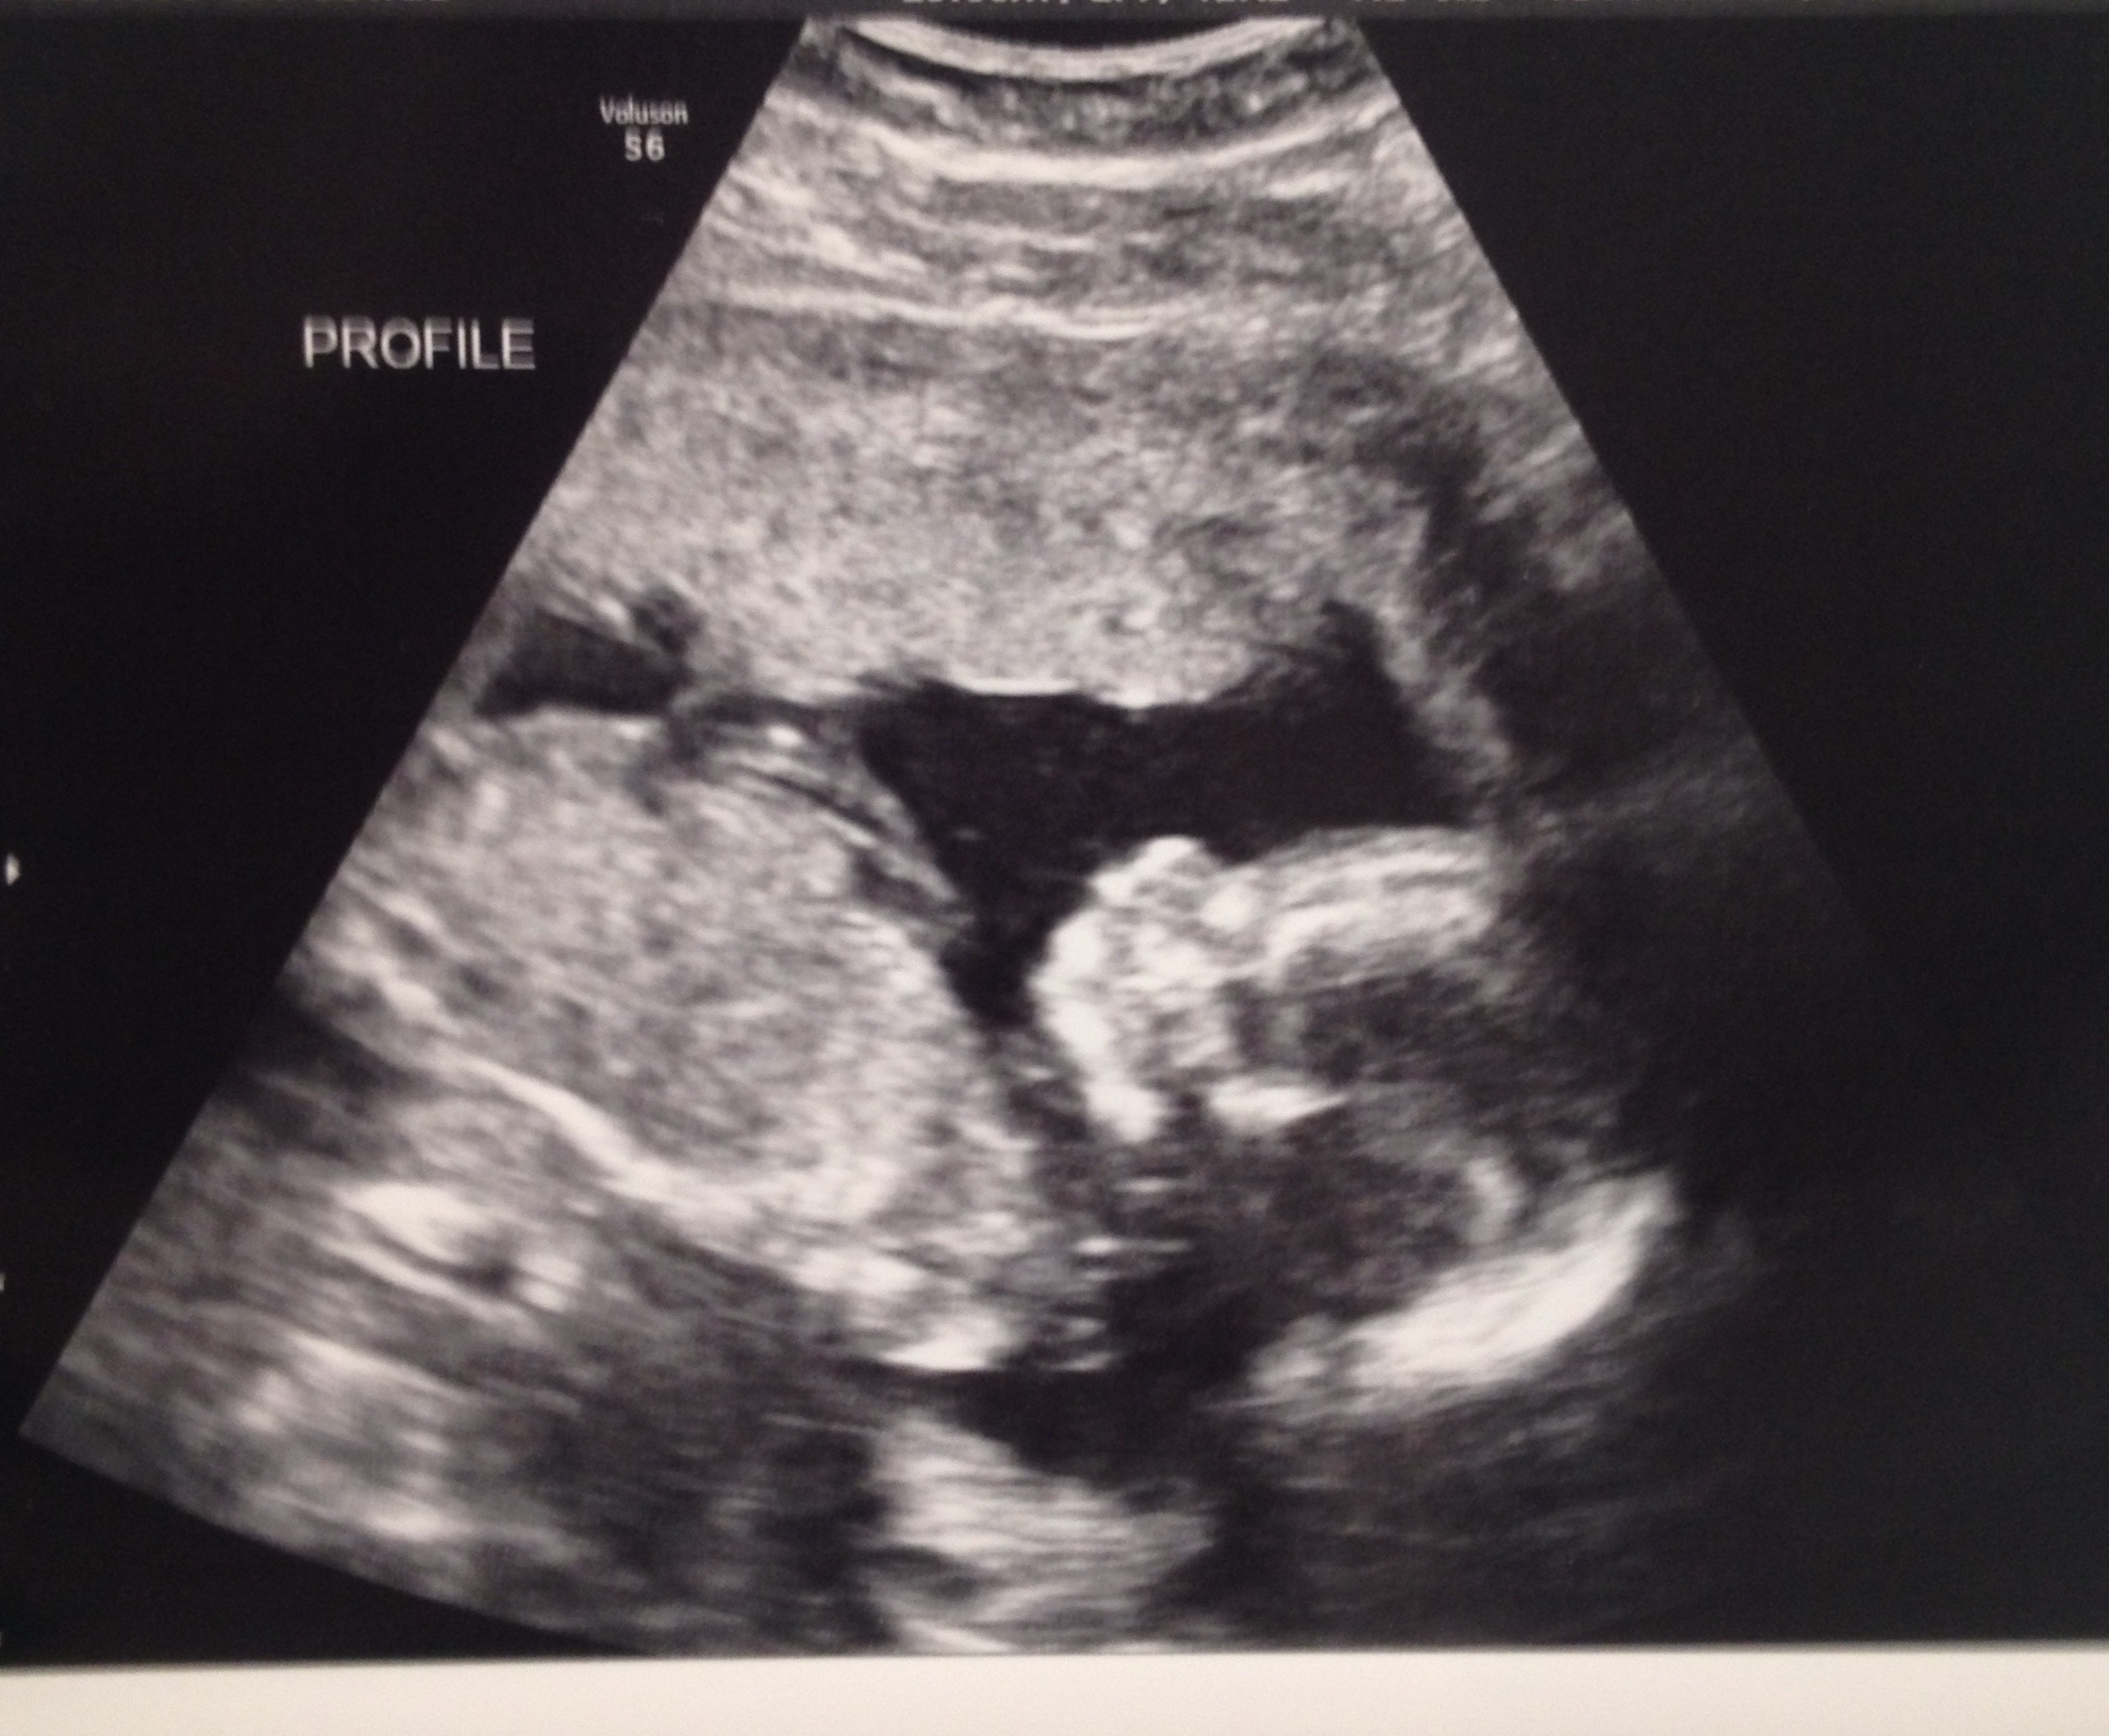

20w5d today (ticker is wrong but haven't updated it yet)

Here is our baby girl last Thursday at our a/s appointment. They found a cyst on her brain called Choroid Plexus Cyst so we have to see a perinatologist to have it looked at further to see if she possibly has Downs Syndrome since it is considered a soft marker. Dr was very positive about the outcome and said she had no other markers and that normally go away but it's just a precaution. Praying for the best! She just started kicking away a few days back and hubby has got to feel her twice already each on a different day. She is also sitting breech for now so hoping she uses the next 19 weeks to get into position : D

I had my A/S today and everything looked perfect. Our little guy was not very cooperative though so I couldn't get a 3D pic. My sister is an ultrasound tech so she will take me in and scan me another time to get some good face pics. Here is his profile with a knee by his mouth and a good one of his feet. He was curled up with his arms and legs covering his face when they tried to do 3D. Little stinker!